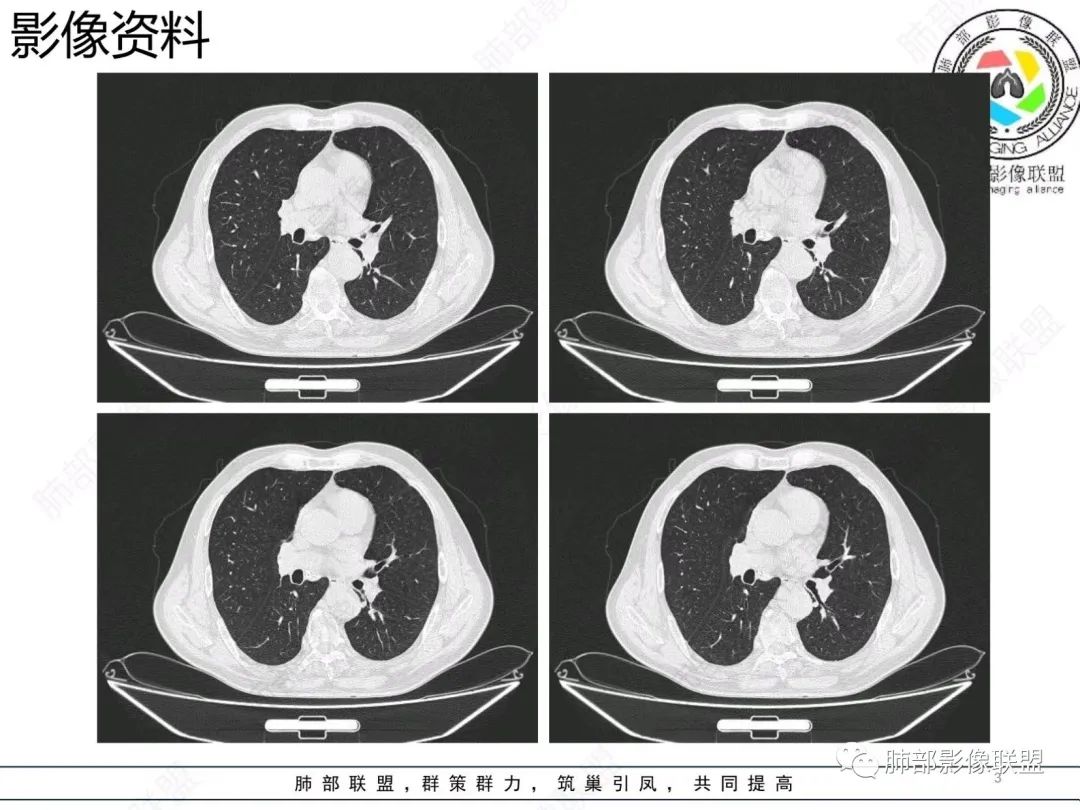

【病例】胸膜下的混合密度结节—良恶之争

老年男性,右肺下叶混合磨玻璃密度结节,可见血管弯征,首先考虑肺腺癌。

右肺下叶背段不规则结节,边界欠清,可见少许晕征,另见胸膜凹陷征及血管弯,考虑腺癌,鉴别隐球菌。

右肺下早不规则结节,周围少许磨玻璃晕,胸膜有牵拉凹陷,虽然部分边界平直,但血管受牵拉弯曲,首先还是考虑肿瘤,腺癌

右肺下叶背段斑片影,边缘平直、局部膨隆,可见磨玻璃密度影,界清,胸膜牵拉,良恶性需要进一步鉴别,倾向隐球,鉴别粘液腺癌。

老年男性,右肺下叶胸膜下结节,边缘见清晰磨玻璃密度影及少许索条,支气管进入后截断,周围血管弯,考虑腺癌,鉴别隐球菌

右肺下叶胸膜下混合密度结节,分叶、毛刺,磨玻璃边界尚清晰,血管集束,支气管进入阻断,考虑腺癌

右肺下叶背段胸膜下肿块,边缘不规则,分叶,毛刺,有磨玻璃,边界清,近肺门侧见血管聚集,支气管进入后闭塞,右肺下叶肺静脉牵拉扭曲。诊断,支持腺癌

老年患者,无呼吸道相关症状,肺部影像学表现:胸膜下占位,有结节融合趋势,内有低密度灶。考虑隐球菌,鉴别腺癌。

胸膜下结节,与胸膜平行,多结节融合,边缘模糊,直边征,考虑炎性肉芽肿,隐球,腺癌

右肺下叶背段实性结节,边缘分叶,较平直,长轴平行胸膜,胸膜增厚,考虑炎性假瘤,隐球菌,鉴别腺癌。

混合性磨玻璃结节,边界清晰,血管打弯,考虑腺癌,鉴别炎性肉芽肿病变。

老年男性,体检发现,无症状,右肺下叶背段肿块影,边缘清楚,无卫星灶,棘状突起,毛刺征,血管集支束,空泡征,考虑恶性肿瘤。

老年男性,体检发现。右肺下叶混合磨玻璃结节,渗漏征,短毛刺,血管集支束,空泡,考虑腺癌。

老年男性右肺下叶靠近胸膜一不规则混合密度影,周围有渗出,内见支气管扩张,考虑炎性病变隐球鉴别腺癌

老年男性 右肺下叶胸膜下见一团状实性病灶+边缘磨玻璃,边缘形态不规则,,局部有平直,长轴平行于胸膜面,整体收缩力偏弱,邻近胸膜面轻度增厚,纵隔窗显示病灶内可见支气管充气,考虑炎性肉芽肿,隐球菌可能,鉴别黏液腺癌。

右肺下叶实行病灶,边缘部分有边界清晰的磨玻璃影,实变明显层面,可见平直。考虑腺癌

右下肺近胸膜病变,周围可见磨玻璃影,界限无法判断清楚?模糊?。考虑右下肺占位:真菌感染?腺癌?淋巴瘤?

右肺下叶胸膜下结节,边界清楚毛玻璃,有分叶、毛刺、血管集束及胸膜增厚,考虑肉芽肿性病变,鉴别于腺癌

右肺下叶实性病灶,局部平直,考虑炎性病变,隐球菌可能

胸膜下结节,长轴与胸膜平行,边缘模糊,直边征胸膜凹陷牵拉不明显,考虑炎性肉芽肿,隐?鉴别腺癌。

右肺下叶后基底段胸膜下斑块影,边缘清楚,有平直和膨隆特点,周围清楚GGO,较模糊(似清非清,邻近见多发纯GGO结节,以肺腺泡分布,主体病灶与胸膜平行,收缩力弱,边缘见支气管充气征,首诊断炎性肉芽肿,抗炎治疗和查下隐球荚膜抗原两方面进行,另取旧片对比,与粘液腺Ca鉴别,最后经皮肺穿刺病理诊断!

上面这些征象存在炎性病变可能,我先考虑炎性病变——隐球,这样的血管弯在肺隐球菌病里也出现过。腺癌尤其是粘液腺癌也不敢排除。建议完善血隐球菌荚膜抗原、经皮肺穿刺活检等检查。